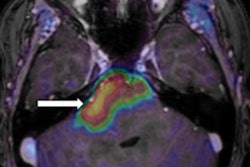

Meanwhile, Swiss researchers have made the headlines this week at the U.S. Society of Nuclear Medicine and Molecular Imaging annual meeting in Denver, Colorado, where a team from Zurich presented new findings on brainstem glioma. Go the Molecular Imaging Community, or click here.